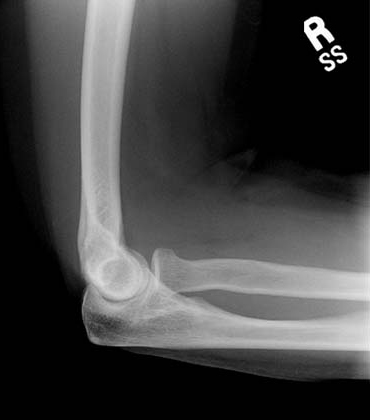

• Capitulum

• Humerus

• Olecranon

• Radial Head

• Radial Neck

• Radial Tuberosity

• Radius

• Trochlear Notch

• Ulna